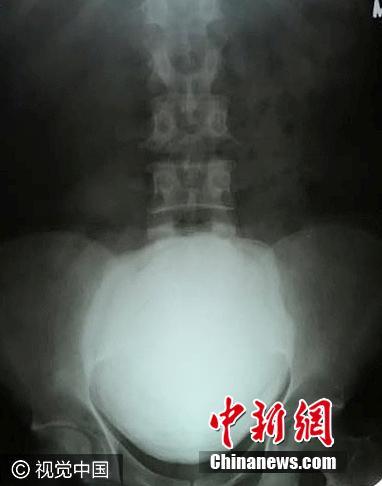

印度男子腹痛入院 膀胱取出1.5公斤巨型結石

近日,印度古吉拉特邦瓦爾薩德縣,49歲的Maheshbhai Rasikbhai Patel因腹部劇痛入院,醫生使用撬棍從病人膀胱取出一顆尺寸為11.5厘米 X 17厘米、重1.5公斤的結石,手術時間持續一個半小時。圖片來源:視覺中國